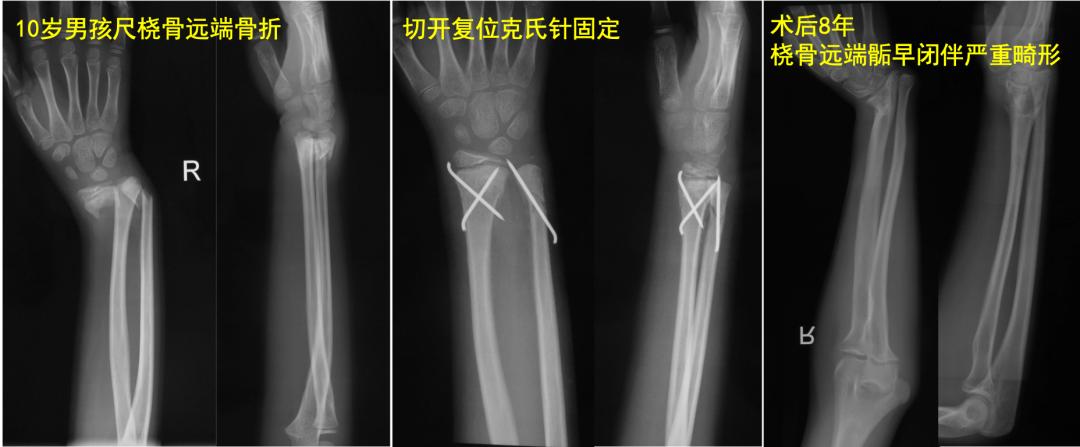

像下面这个10岁孩子,前臂远端骨折手术后8年,桡骨远端骺板早闭出现严重腕部畸形。所以,需要警惕,儿童“骺板”其实是把双刃剑,保护好了才能利于治疗,一定不能损伤它。